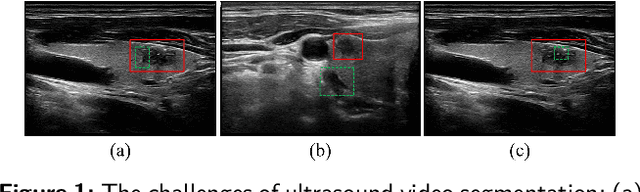

Medical ultrasound videos are widely used for medical inspections, disease diagnosis and surgical planning. High-fidelity lesion area and target organ segmentation constitutes a key component of the computer-assisted surgery workflow. The low contrast levels and noisy backgrounds of ultrasound videos cause missegmentation of organ boundary, which may lead to small object losses and increase boundary segmentation errors. Object tracking in long videos also remains a significant research challenge. To overcome these challenges, we propose a memory bank-based wavelet filtering and fusion network, which adopts an encoder-decoder structure to effectively extract fine-grained detailed spatial features and integrate high-frequency (HF) information. Specifically, memory-based wavelet convolution is presented to simultaneously capture category, detailed information and utilize adjacent information in the encoder. Cascaded wavelet compression is used to fuse multiscale frequency-domain features and expand the receptive field within each convolutional layer. A long short-term memory bank using cross-attention and memory compression mechanisms is designed to track objects in long video. To fully utilize the boundary-sensitive HF details of feature maps, an HF-aware feature fusion module is designed via adaptive wavelet filters in the decoder. In extensive benchmark tests conducted on four ultrasound video datasets (two thyroid nodule, the thyroid gland, the heart datasets) compared with the state-of-the-art methods, our method demonstrates marked improvements in segmentation metrics. In particular, our method can more accurately segment small thyroid nodules, demonstrating its effectiveness for cases involving small ultrasound objects in long video. The code is available at https://github.com/XiAooZ/MWNet.